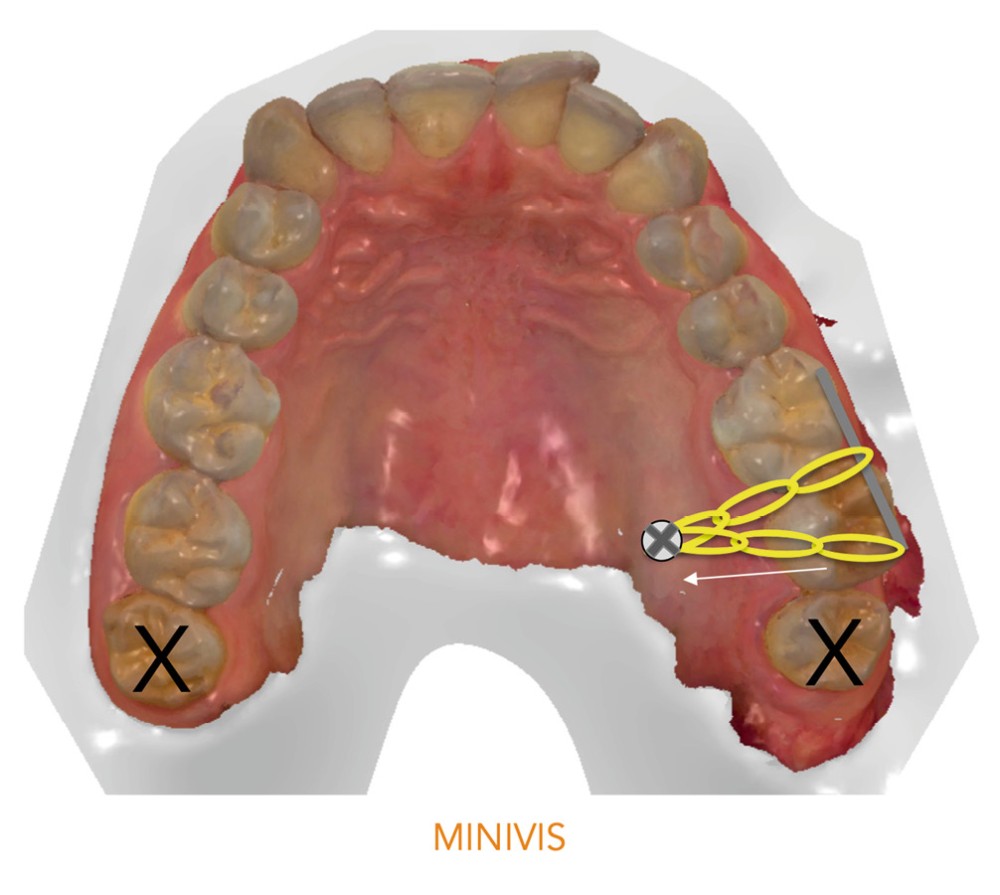

- la première utilisant une minivis pour repositionner sur l’arcade la 27 [1] ;

Dans un premier temps (fig. 2), la 28 (et la 18) a été extraite pour faciliter le déplacement de la 27 (DDM postérieure). Une minivis palatine a été placée entre 26 et 27 et des boutons ainsi qu’un sectionnel collés sur les faces vestibulaires des 26 et 27. Des chaînettes élastomériques ont été ancrées sur les boutons et la minivis, en passant au-dessous des faces occlusales de ces dents. Les chaînettes reliant un dispositif vestibulaire et un palatin et prenant appui sur les faces occlusales des molaires du secteur 2, les mouvements dentaires induits sont un déplacement vestibulo-palatin associé à une ingression des 26 et 27. Les minivis sont des ancrages absolus qui ne nécessitent pas d’utiliser l’ancrage des dents adjacentes ou antagonistes, ce qui préserve d’effets sur ces dernières.